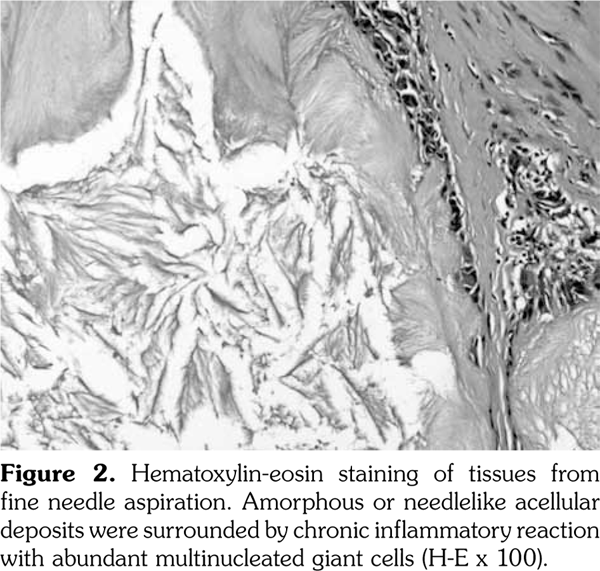

A 54-year-old male patient was admitted to our department with palmar numbness and disability for two years. He had a history of gout for 30 years but received no treatment. Physical examination revealed obvious subcutaneous tophi and thenar muscle wasting. Flexion deformity of his metacarpophalangeal and interphalangeal joints is shown in Figure 1a. Positive Tinel’s sign and Phalen’s maneuver were present. Routine laboratory test showed high level of uric acid (608 μmol/L). The electrophysiological examination revealed sensory and motoring demyelinating and axon lesions in both median nerve, especially in the right hand, which supported the diagnosis of CTS. Furthermore, DECT showed extensive monosodium urate crystals in the intercarpal and radiocarpal joints with compression overlying the flexor tendons (Figure 1b, c). We also observed punched-out bony erosions in the carpal bones (Figure 1d). These aspects indicated severe and typical CTS caused by gouty tophi, which was further confirmed by biopsy of fine-needle aspiration (Figure 2). Surgery was recommended, but the patient refused to undergo surgery and chose to receive febuxostat. Uric acid level had decreased in the next six-month follow-up with little improvement for his numbness and deformity. A written informed consent was obtained from the patient.